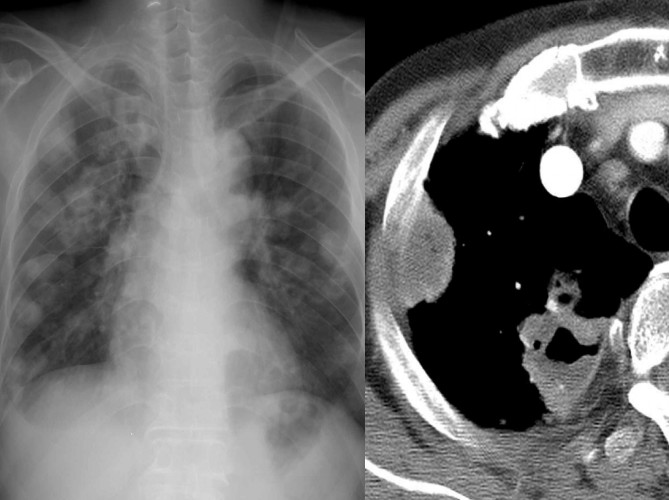

病例1:肺结核

X线胸片表现为在两侧中上肺有斑片状阴影,隐约可以看到小的空洞样病变。CT显示的很清楚,可以看两肺尖空洞,周围有小的点状播散病灶。在上叶前段、左上叶尖后段也有空洞,这些空洞的周围可以看到树芽征,小叶中心的病变。所以这是典型的以中上肺分布的伴支气管播散病灶,为典型的肺结核病变。